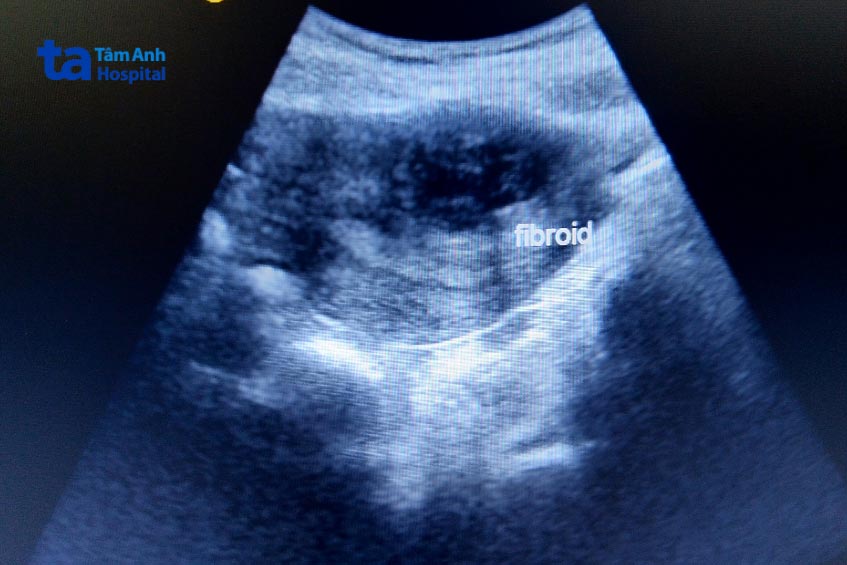

Với sự phát triển mạnh mẽ của y học cùng sự hỗ trợ của máy móc thiết bị tối tân, kỹ thuật siêu âm có khả năng phát hiện được các khối u xơ ẩn sâu phía trong. Đầu dò của sóng siêu âm có thể giúp bác sĩ phát hiện được cả những khối u xơ nhỏ nhất tồn tại ở phía bên trong tử cung.

Với sự phát triển của máy móc thiết bị, hiện nay hình ảnh siêu âm được thể hiện rõ nét và chân thật, nhờ đó có thể phát hiện, đánh giá và theo dõi u xơ tử cung. Chính vì thế, siêu âm là phương pháp hữu ích giúp bác sĩ có thể chẩn đoán chính xác tình trạng u xơ để đưa ra các hướng dẫn điều trị thích hợp, hiệu quả.

Siêu âm có thể nhận diện và phát hiện u xơ tử cung – một loại u lành tính thường phát triển trong cơ hoặc ở thành tử cung. Ngoài ra, siêu âm còn giúp phát hiện các bất thường khác trong tử cung hoặc ở các cơ quan lân cận như buồng trứng nếu có.

Siêu âm cũng giúp phân loại và cho các thông tin cụ thể về vị trí, số lượng và kích thước các khối u xơ. Thông tin này rất quan trọng giúp bác sĩ đánh giá được mức độ nghiêm trọng và ảnh hưởng, từ đó đưa ra hướng dẫn điều trị thích hợp.

Một nghiên cứu(3) đăng tải trên Tạp chí Y học Việt Nam cho kết quả: trong chẩn đoán u xơ tử cung siêu âm có độ chính xác 93,1%. Kết luận siêu âm có độ chính xác cao trong chẩn đoán u xơ và tổng quát vùng chậu trước phẫu thuật. Kích thước tử cung qua khám lâm sàng có mối tương quan khá chặt chẽ với kích thước tử cung thông qua siêu âm.